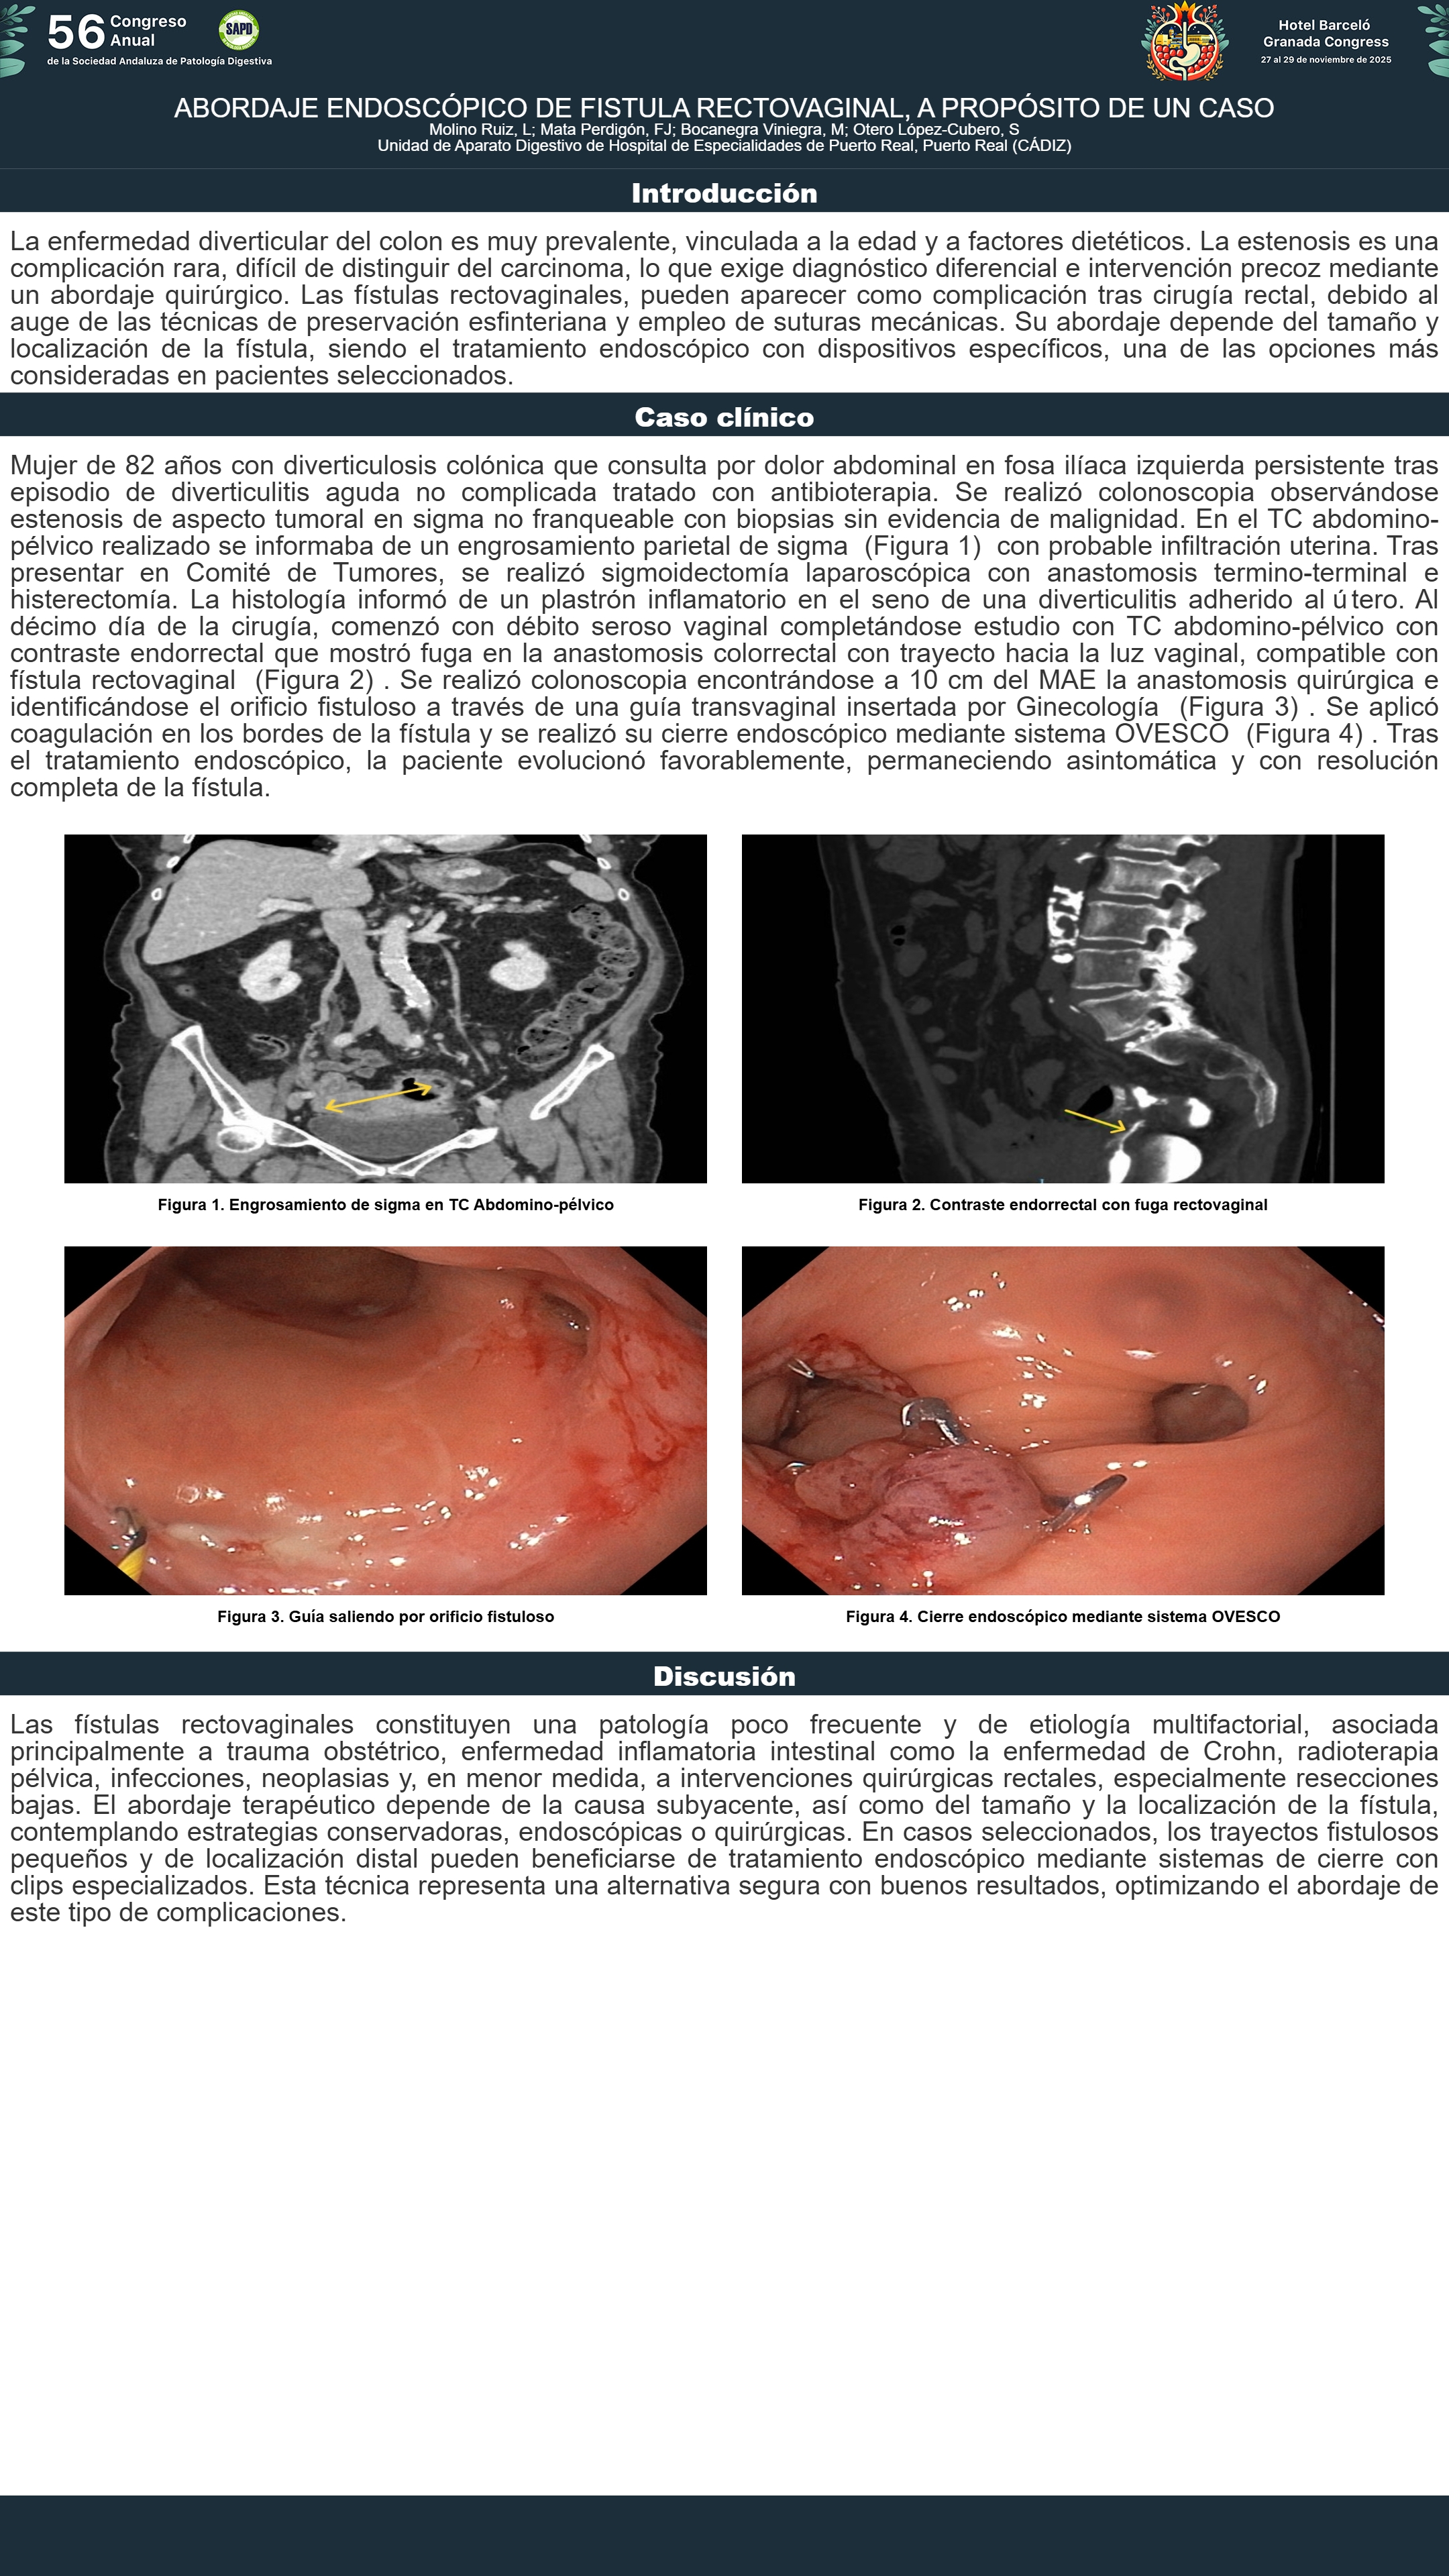

[CP-004] ABORDAJE ENDOSCÓPICO DE FISTULA RECTOVAGINAL, A PROPÓSITO DE UN CASO